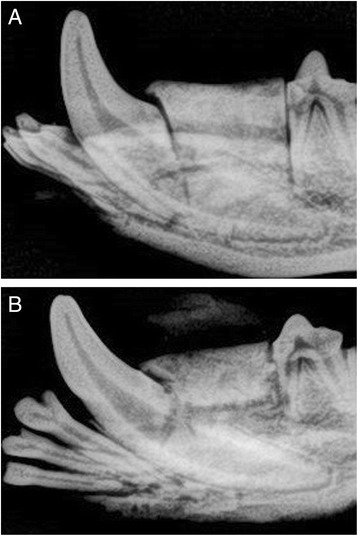

Radiographic examination revealed clear margins separating newly inserted scaffolds from surrounding bone defect (Fig. 4a). After completion of healing time, the margins between the scaffold and bone defect became less demarcated due to deposition and ingrowth of new bone (Fig. 4b).

Fig. 4.

a Peri-apical X-ray of zirconia scaffold immediately placed in bone defect. Margins between scaffold and bone are clearly demarcated. b Peri-apical X-ray of zirconia scaffold after completion of healing time. Margins between bone defect and scaffold are less demarcated due to new bone growth